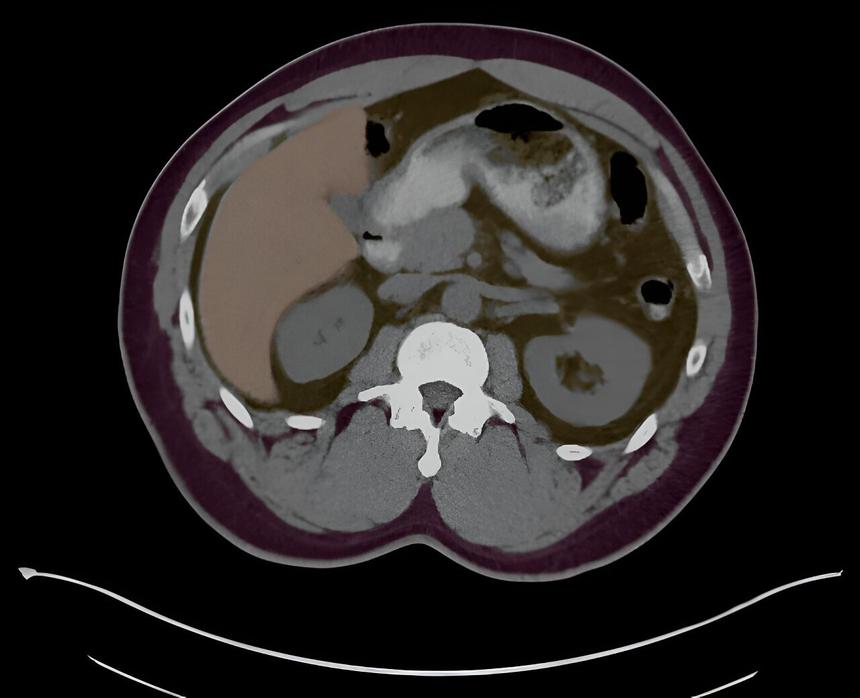

В медицине искусственный интеллект (ИИ) проявляет себя как мощный инструмент для улучшения диагностики. Система Penn AInSights, разработанная в Penn Medicine, была признана одним из лучших решений в области радиологии и значительно повышает точность визуализации внутренних органов.

Система создает трехмерные модели, анализируя изображения, что позволяет врачам точно определять наличие аномалий, таких как жировая болезнь печени или признаки диабета. Это знание дает возможность медперсоналу принимать меры по лечению пациентов на ранних стадиях заболеваний, потенциально увеличивая продолжительность их жизни.

Искусственный интеллект в Penn AInSights был обучен на тысячах изображений и теперь автоматически генерирует аннотации и количественные характеристики, что экономит время и упрощает процесс диагностики. Система позволяет врачам проводить дополнительные проверки, выявляя незамеченные проблемы, и даже помогает в диагностике деменции, анализируя изменения в объеме мозга.